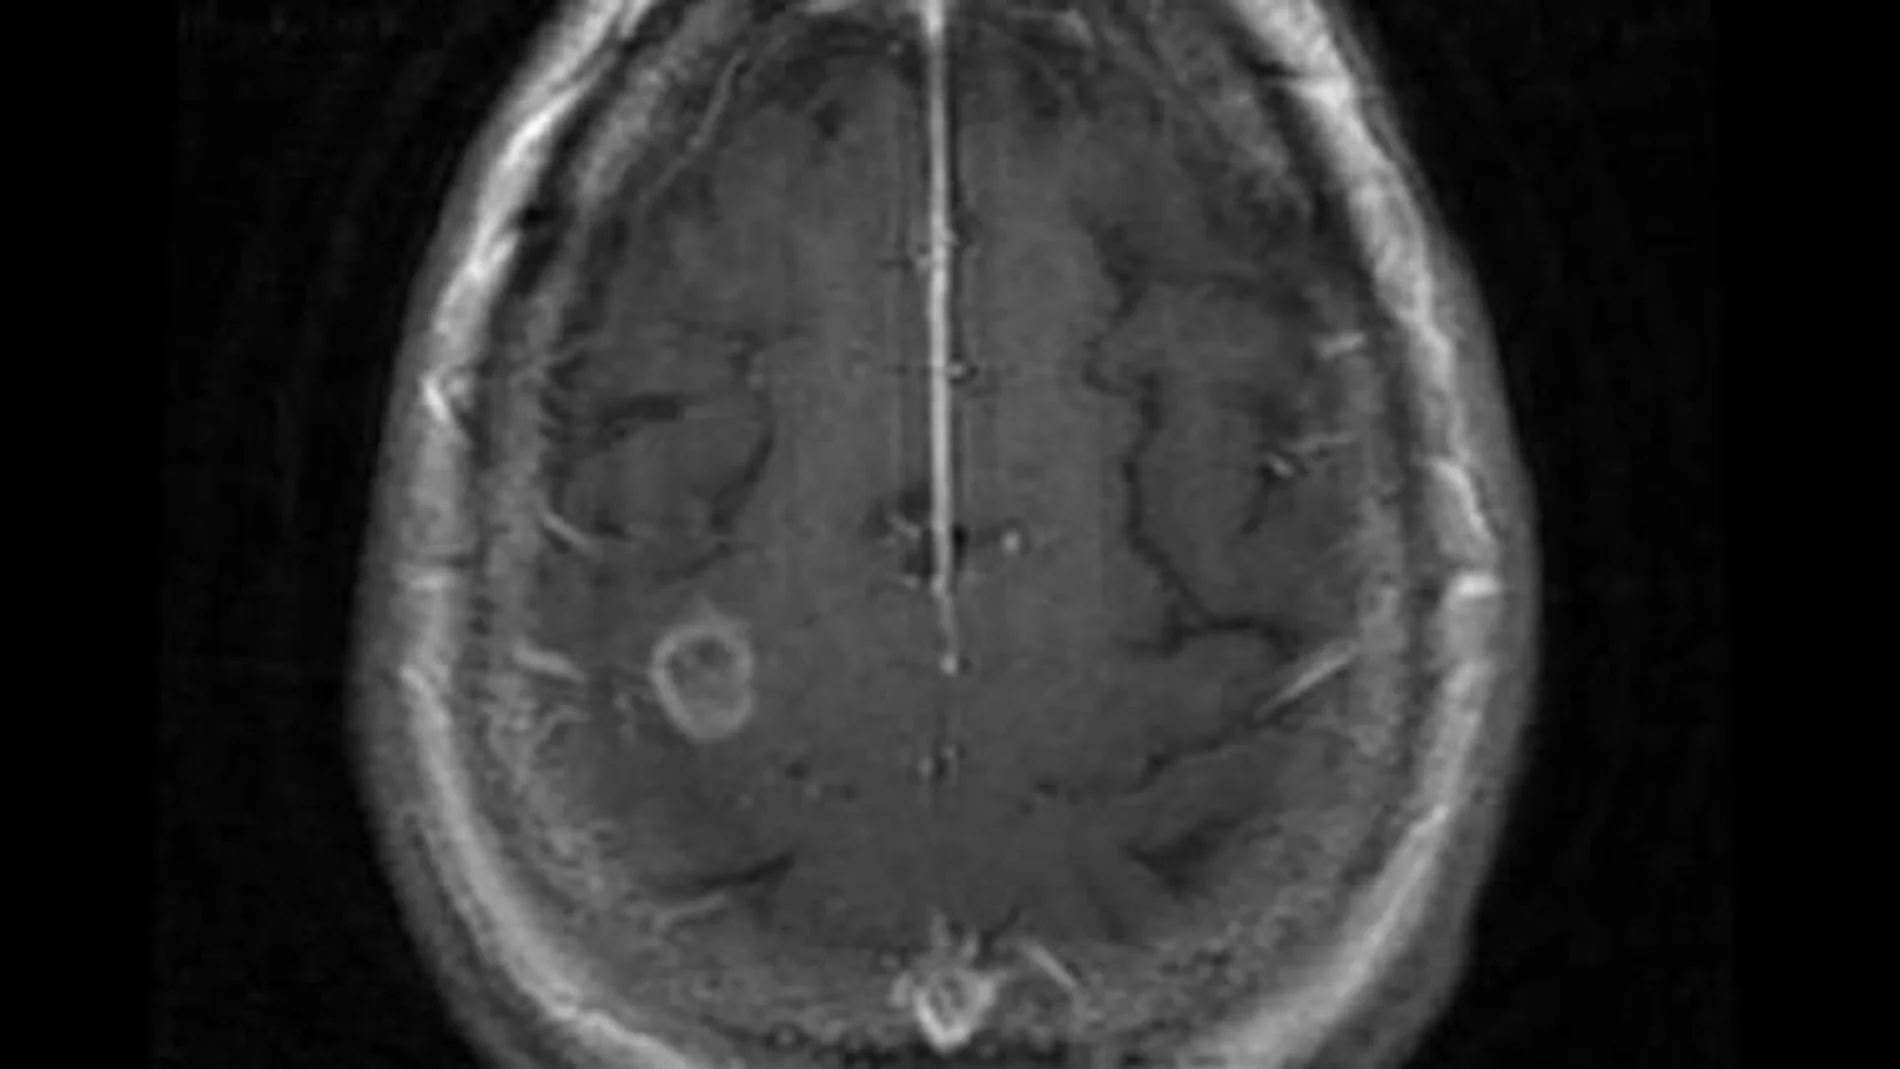

El portal Mayo Clinic señala que la infección por Naegleria provoca una enfermedad conocida como meningoencefalitis amebiana primaria, que provoca inflamación del cerebro y destrucción del tejido cerebral.